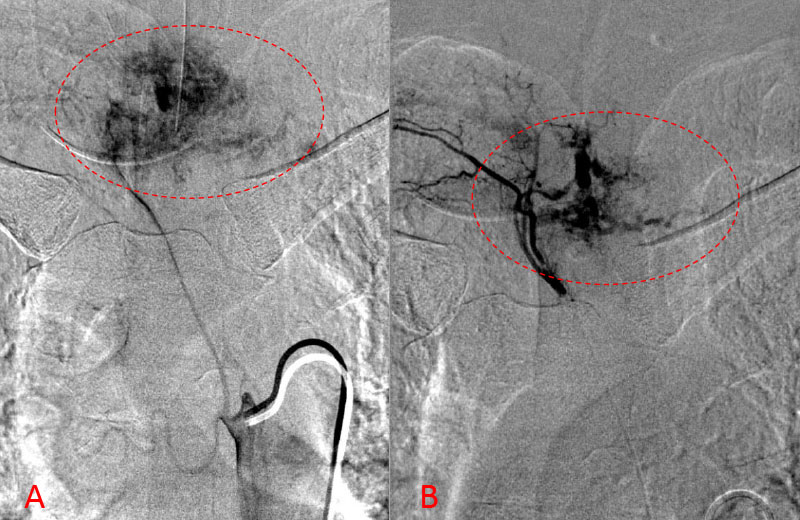

Spinal angiography showed a very hypervascular lesion fed predominantly by the right supreme intercostal artery (Figure 2. A, B).

Figure 2. A, B) Selective angiography of the right supreme intercostal artery demonstrates extensive hypervascularity of this aggressive T3 hemangioma.